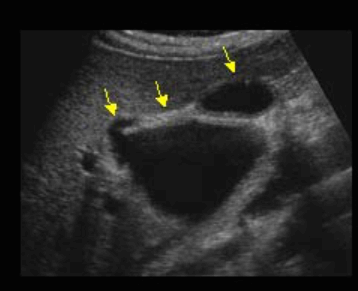

US finding

- 간내담관은 확장되고 간외담관은 정상이다.

- 담낭은 위축되며, 간외담관은 담즙 흐름이 없는 담관으로 묘출된다.

- 폐쇄된 담관부위에 종양의 윤곽이 보일 수 있으나 초음파상 발견하기 어렵다.